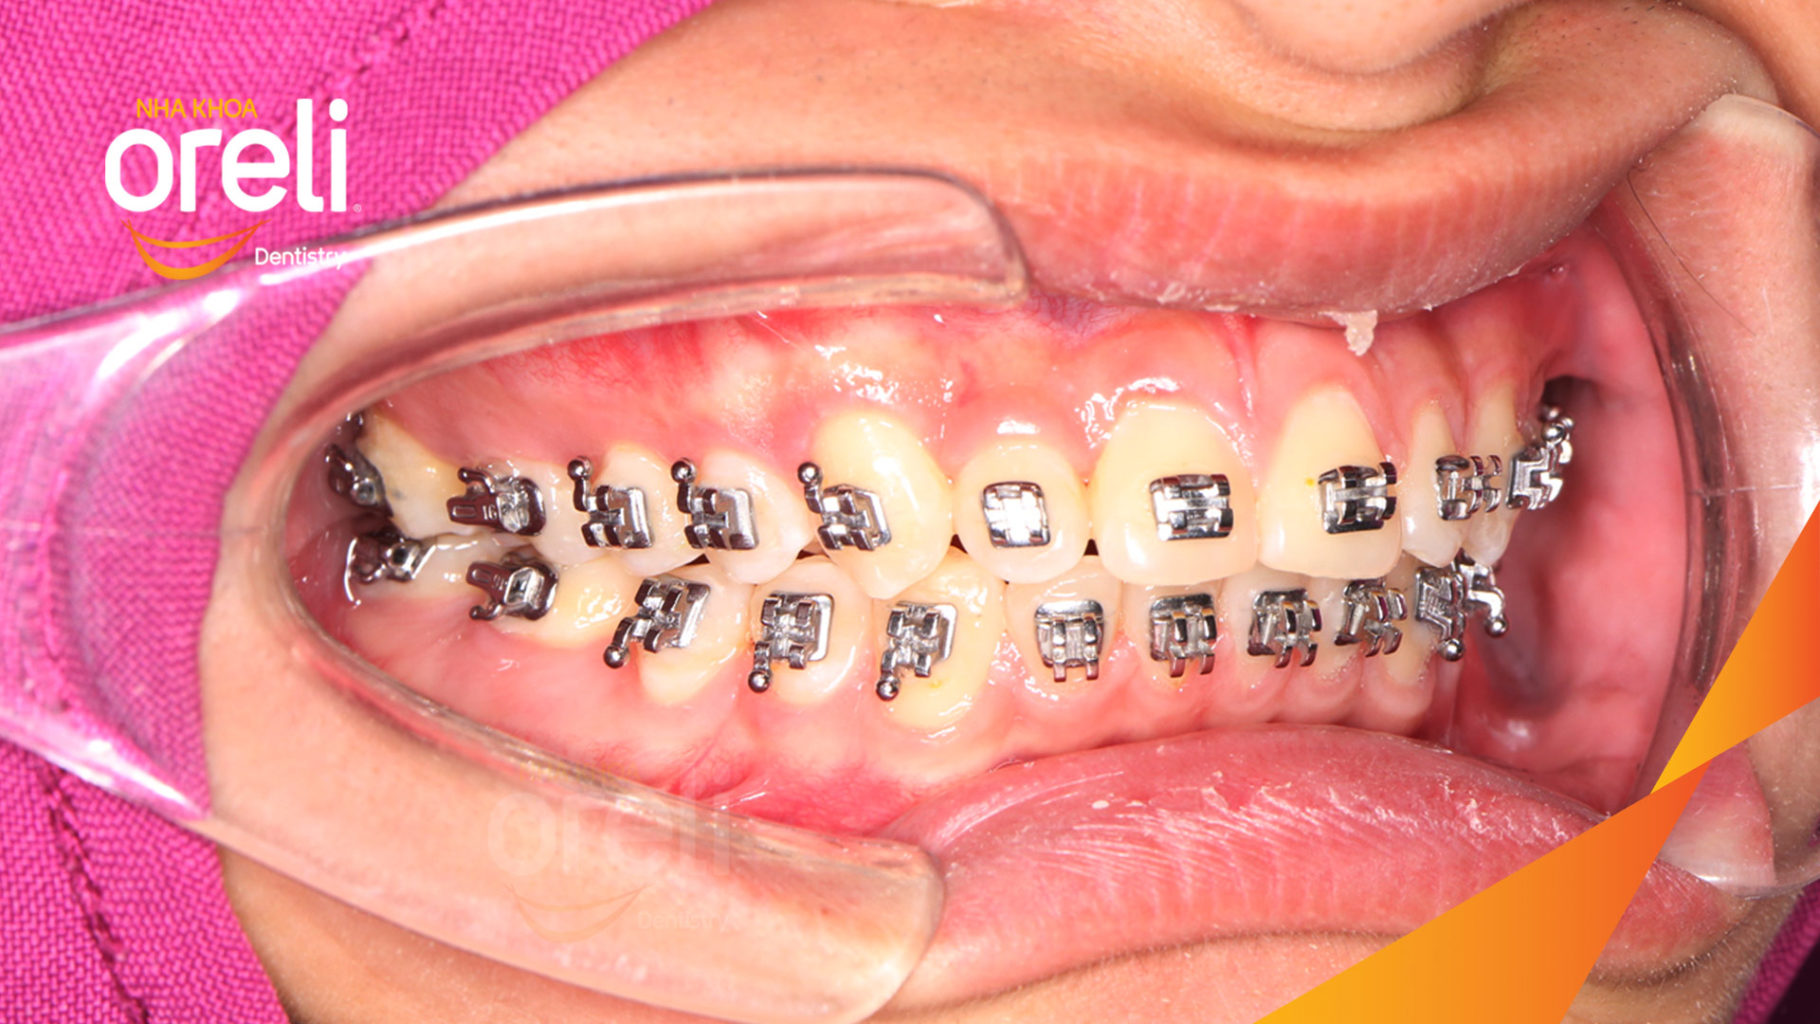

Giải pháp: làm đều chỉnh khớp cắn sâu không nhổ răng

Thời gian: 36 tháng

Kết quả: khớp cắn đúng, cằm tiến ra trước với mặt nghiêng đẹp

Hình ảnh thực tế